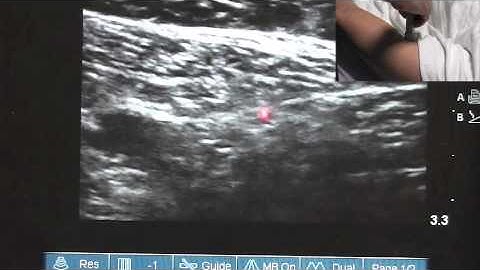

How To: Ultrasound Guided Saphenous Nerve Block 3D Video